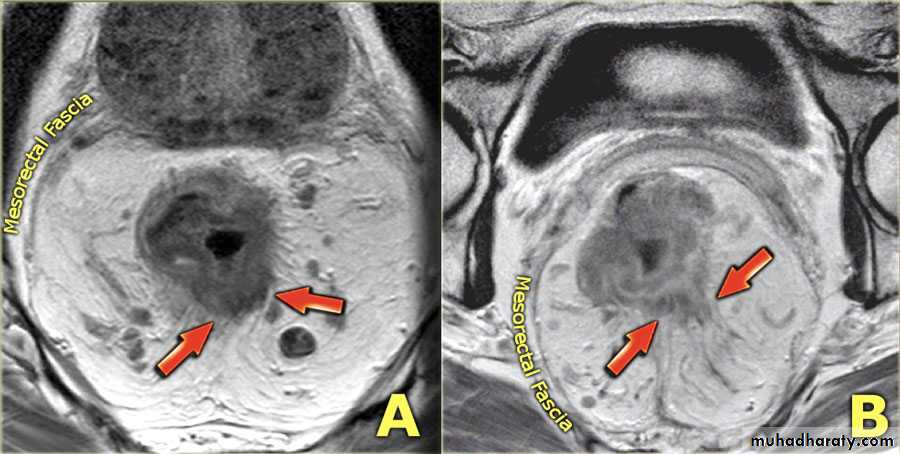

Staging of CRC

• Staging of colorectal carcinoma may be summarized as follows:

• Stage I: tumor confined to the bowel wall

• Stage II: invasion through the full thickness of the bowel wall, invasion of adjacent structures

• Stage III: metastasis to regional lymph node(s)

• Stage IV: metastasis to distant site(s) such as liver, non-regional lymph node(s), lung.

• The two most critical factors influencing survival data in CRC are

• Depth of invasion of the bowel wall

• Presence or absence of lymph node metastases.

• MRI and trans-rectal US (TRUS) are able to differentiate the layers of the rectal wall. These modalities are therefore able to assess accurately the depth of invasion of rectal tumor.